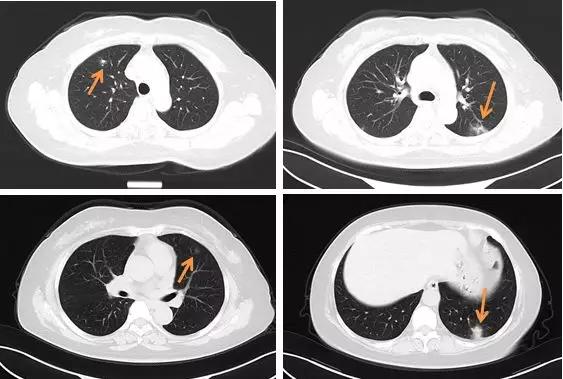

病例 5 女性,35 岁,发热待查

左肺上叶斑片状渗出、部分实变,内见支气管充气征

上述病例均为新型冠状病毒肺炎确诊病例

最为典型和有特征的早期表现:

胸膜下斑片状磨玻璃影,多发、单发都可以;其纹理可呈网格样(铺路石征)

混合磨玻璃及晕征

支气管充气征

形态:扇形、球形